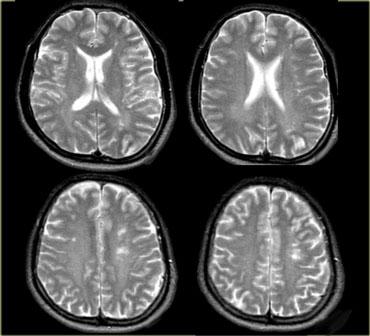

Bên trái là hình ảnh chuỗi xung T2W của bệnh nhân bị nhồi máu trong vùng tưới máu của động mạch não giữa (MCA).

Lưu ý rằng các động mạch xuyên thấu kính – vân bên của MCA cũng bị tổn thương (mũi tên màu cam).